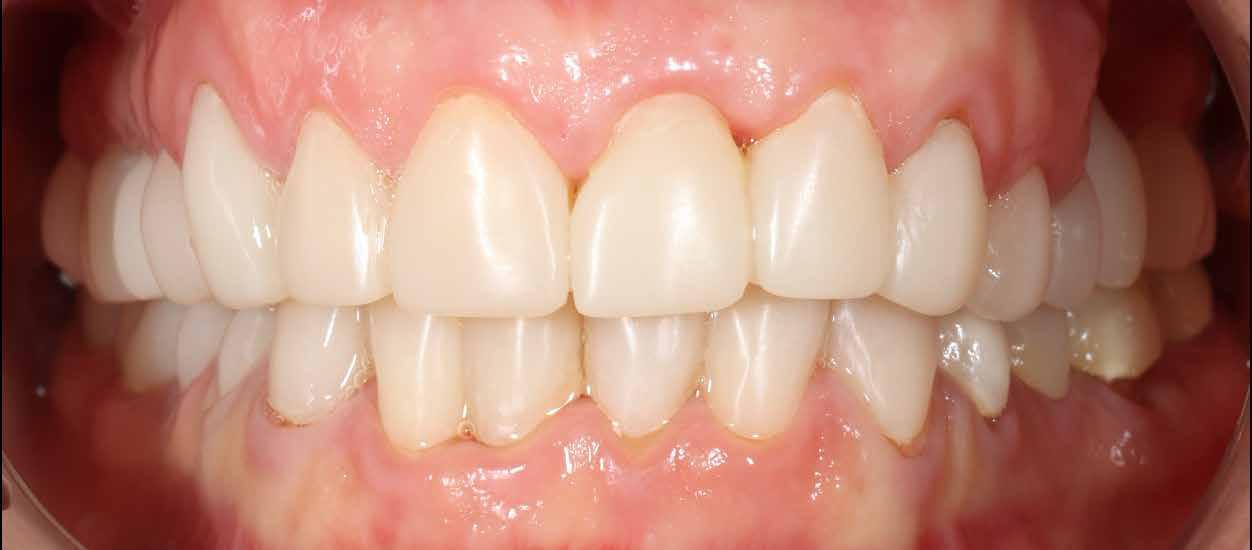

A cikkben egy fiatal nő kezelésének interdiszciplináris megközelítését foglaltuk össze, aki fogászati állapota miatt hoszszú ideje szenvedett fizikálisan és pszichésen is (1. ábra)

1. a–c ábrák: Kiindulási helyzet: fiatal páciens komoly fizikai és pszichés szenvedéssel.

A fogak extrahálása és az alveoláris plasztika teljes narkózis mellett történt meg, így teremtve ideális helyzetet a protetikai ellátáshoz. A műtéti beavatkozás után a páciens az ideglenes fogsorral távozott. Egy héttel később jött kontrollra. Nemcsak látványra változott meg nagymértékben, hanem egyértelműen magabiztosabb és önbizalommal teli volt a fellépése (12. ábra)

Az elsődleges terápiás szakasz kulcsfontosságú volt a teljes rehabilitáció szempontjából. A páciensnek nem csak szép, esztétikus mosolyt kölcsönzött, hanem életminőségének javulását is hozta (13. ábra). A Digital Denture folyamatnak köszönhetően a kezelés ráfordításai is alacsonyak voltak. A fiatal nő messzemenően boldog, magabiztos és motivált a következő lépéshez.

12. ábra: Páciensünk egy héttel fogainak extrahálása és az ideglenes fogsor azonnali behelyezése után. 13. a–d ábrák: Látványos átalakulás: kezelés előtt és után. A páciens maga hangsúlyozta ki életminőségének jelentős javulását.